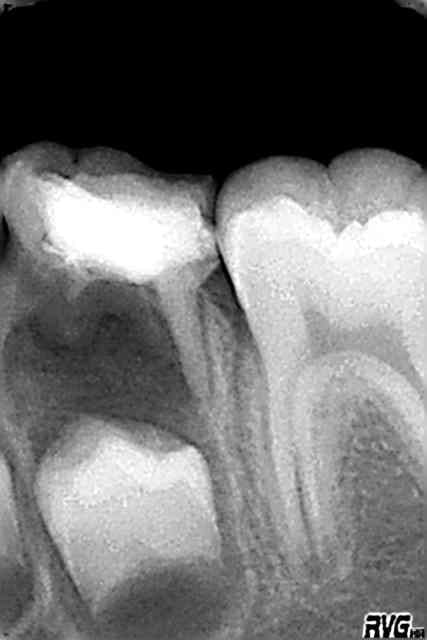

Radio rd5fn3 - Eugenol

ça y est 35 est pratiquement en place,une légère rotation

Dans le cas que tu présentes, est-ce que l'éruption de la 6 n'a pas été stoppée par le mainteneur, bloqué par la contre-dépouille distale de la 4 ? On a l'impression que 36 est au même stade presque deux ans plus tard.